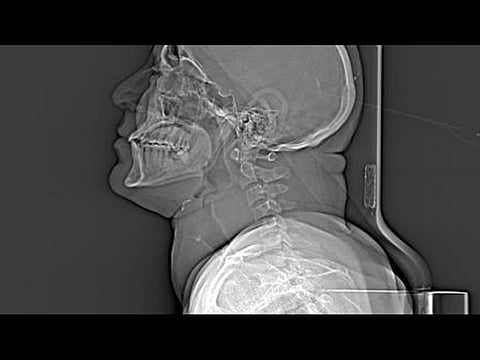

Huge tumour was obstructing the breathing and swallowing reflexes of patient

Dubai: In a rare surgery lasting five hours, doctors excised a thyroid gland weighing 550 gms from the neck of a 46-year-old expatriate.

“Clinical examination of the patient indicated that his colloid goitre had grown into a mass measuring 18 x 16cm involving most of the neck down to the anterior border,” Dr Goel said.

“Excision of the entire gland was challenging as the mass growing on it was affecting the vital carotid artery and internal jugular vein as also compressing the trachea,” said Dr Rahul Tugnait, specialist in General Surgery at the hospital. “The trachea is made of soft cartilage and there was danger of slicing through it.” Any mistake could rupture either the carotid artery or jugular vein or cause respiratory distress to the patient.